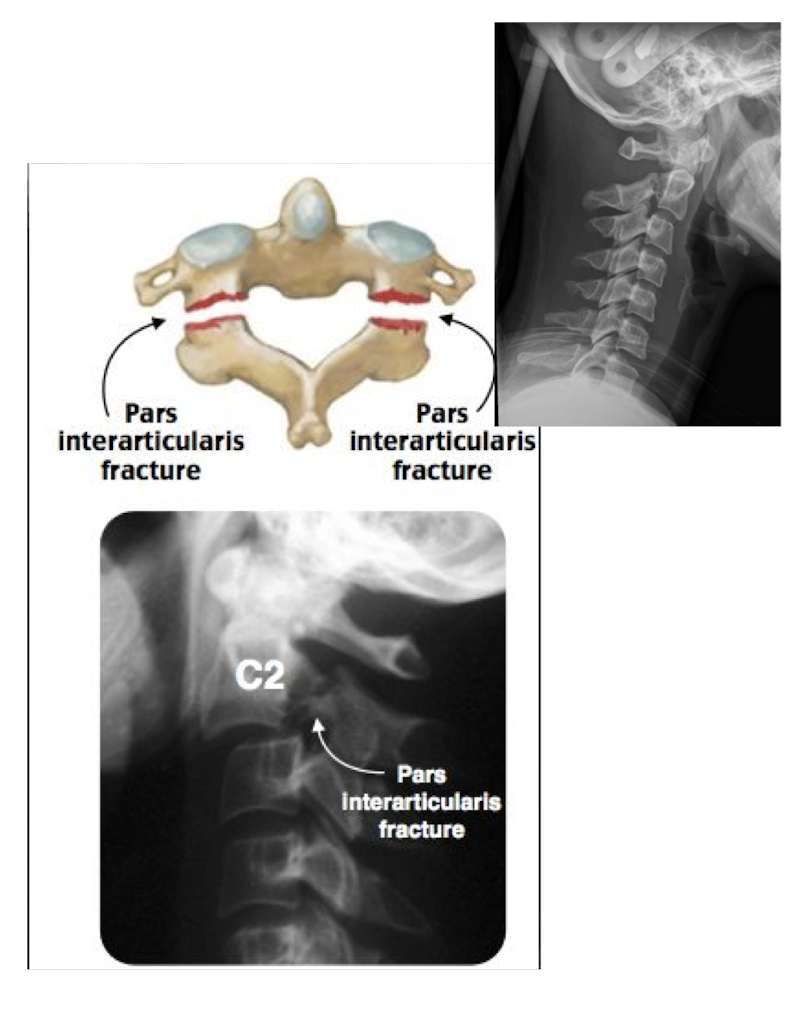

Fracture of C2: Hangman’s Fx

What type of Fx is this?

Bilateral Fx of the pedicles of C2 w dislocation of vertebral body C2 on C3

Fracture of C2: Hangman’s Fx

MOI:

__ for info on the SC

Stable or Unstable Fx

MOI:

Hyper Extension Injury in MVA

MRI

Unstable